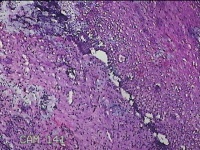

宫颈锥切物

女

31岁

宫颈上皮内瘤变

妇检发现宫颈CIN2 2个月。

灰白暗红色组织2.8x1.8x0.3cm一块,表面糜烂,切面灰白暗红色,质软。

所提供图片不具有诊断价值。

为什么不拍鳞状上皮呢?